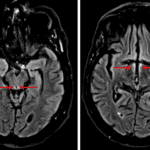

- Central T2/FLAIR signal hyperintensity in the pons with a rim of restricted diffusion and peripheral sparing

- Areas of faint T2/FLAIR signal hyperintensity in the periaqueductal gray matter, medial thalami, and hypothalamus

- Osmotic demyelination

- Possible Wernicke encephalopathy

Central T2/FLAIR signal hyperintensity in the pons concerning for osmotic demyelination syndrome. Recommend correlation with serum sodium measurements.

Areas of faint T2/FLAIR signal hyperintensity in the periaqueductal gray matter, medial thalami, and hypothalamus, which can be seen with Wernicke encephalopathy.